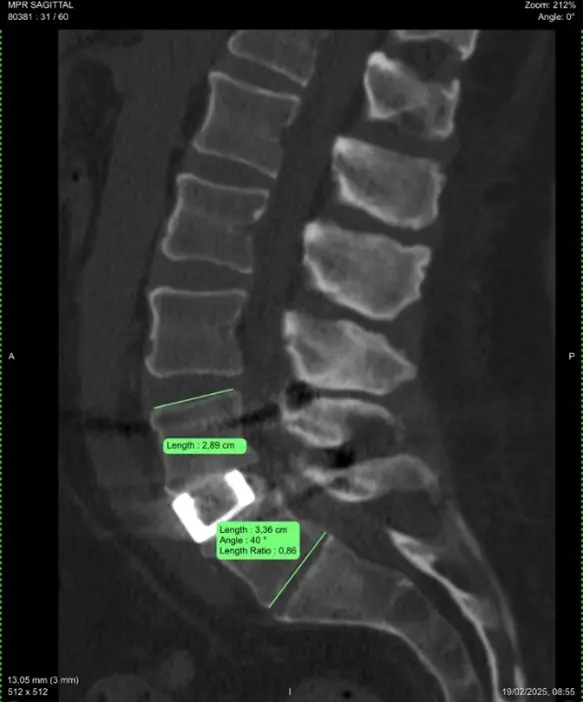

Przy wykonaniu pierwotnej stabilizacji u pacjenta wystąpiły problemy z implantem i nie dało się go stabilnie ustawić. Po kilku miesiącach implant „powędrował” do tyłu, co widać na zdjęciu. Przemieszczenie implantu spowodowało kolizję z korzeniem. Pacjent początkowo czuł się dobrze, jednak powróciły dolegliwości bólowe nie tylko kręgosłupa, ale także kończyn dolnych.

W trakcie operacji rewizyjnej odtworzono odpowiedni kąt lordozy. Było to trudne, aby dostać się do uszkodzonego implantu przez kanał kręgowy i wyjąć go przez wąski otwór.

„Ostatecznie w takich przypadkach walczymy o kąt lordozy, tak aby segmenty kręgosłupa były dalej ruchome. Uzyskaliśmy kąt 40 stopni, co oznacza bardzo dobry wynik leczenia operacyjnego” – wyjaśnia lek. Jurij Kseniuk.